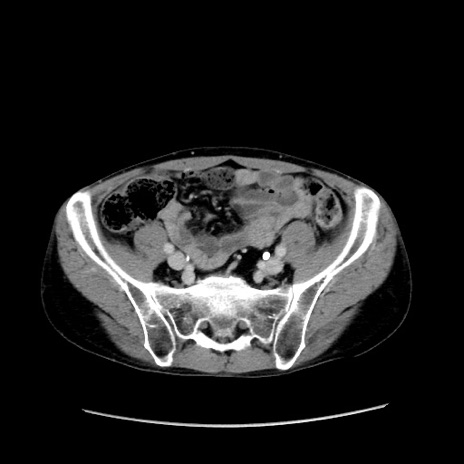

冠状断像